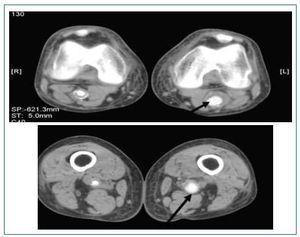

En ausencia de manifestaciones secundarias a la enfermedad de Bechet en los últimos años se optó por suspender la ciclosporina. En los meses siguientes presento lesiones cutáneas compatibles con eccema seborreico en cuero cabelludo y cara, disminución de agudeza visual en probable relación con nuevo brote de uveítis. Se había solicitado angioTAC de miembros inferiores previo a inclusión en lista de espera de trasplante renal en el que se apreciaba en la porción distal de la arteria femoral superficial una dilatación aneurismática hasta la arteria poplitea (fig. 1).

Figura 1.